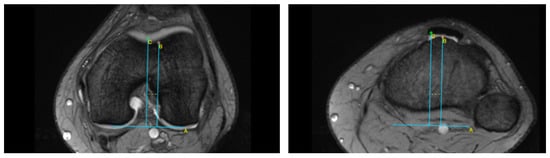

2.2. MRI Analysis

| TT–TG | tibial tuberosity–trochlear groove |

| TT–PCL | tibial tuberosity–posterior cruciate ligament |